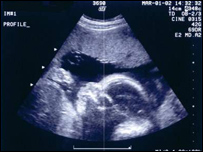

په عادي حالت کې د مور په خېټه کې د ماشوم د بدن د جوړښت او ودې وخت (٤٠) او ياهم له هغې نه کم تر(٣٦) اوونيو دی چې پدې وخت کې ماشوم بايدنړۍ ته سترګې پرانيزي. په افغانستان کې د يوشمېرميندو ماشومان د ياد وخت په دننه کې نه پيدا کيږي چې دا کار دماشوم دمړينې خطرله ځان سره لري. په ملالۍ زېږنتون کې ديوې مېرمنې، چې دنوم له ښودلو يې ډډه کوله، دزېږون د وخت دتېرېدوله امله دوه ماشومان مړه دنياته راغلي وو. په کابل کې د ملالۍ روغتون ډاکټرې نجم السما شفاجو وويل: "کله چې ديوې حاملې مېرمنې دماشوم د پيدايښت نېټه تېره شي،دهغې کڅوړې مايع کميږي چې ماشوم پکې وي. ددې سربېره پلاسنتا(جوړه) هم د(٤٠) اوونيوترتېرېدو وروسته سختيږي اوپه منظم ډول نشي کولای جنين ته وينه ورسوي چې پدې توګه جنين خرابيږي." ډېری مېرمنې دزېږون د دقيقې نېټې دنه ټاکلويا په يادنه ساتلوله امله له داشان خطرونو سره مخ کيږي. د ډاکټرانو په وينا د التراساوند معاينات د حامله ګۍ په لومړيو درېو مياشتو کې کولای شي دزېږون دقيقه نېټه وټاکي.  | | | د التراساوند معاينات د حامله ګۍ په لومړيو درېو مياشتو کې دزېږون دقيقه نېټه ټاکلی شي.. |

ديادونې وړده چې د ولادت سمه نېټه د مېرمنو د مياشتني عادت له وروستۍ ورځې څخه شمېرل کيږي. هغه شمېر ميرمنې چې دا نېټه يې په ياد نه وي، دحاملګۍ په لومړيودريومياشتوکې دې له معالج ډاکتر څخه پدې برخه کې مرسته وغواړي اولازمې مشورې دې واخلي. |